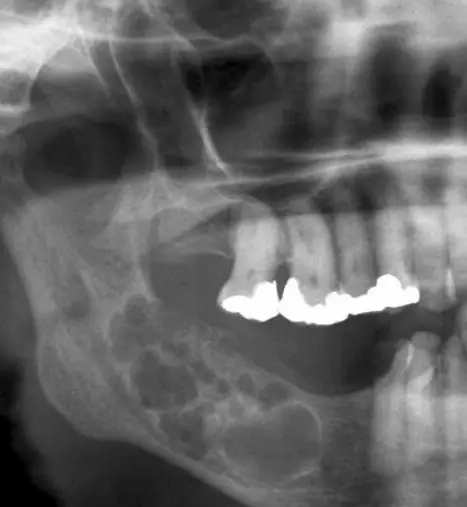

Откриха Амелобластома след направена снимка, предстои спешна операция They found Ameloblastoma after taking a picture, emergency surgery is coming

Здравейте, След като беше направена снимка, се установи наличие на амелобластома – рядък, но агресивен тумор. Въпреки че амелобластомът е неканцерогенен, неговото бързо разпространение и инвазивен характер налагат спешни мерки. Проби от тумора са изпратени за по-нататъшно изследване, за да се определи неговият точен характер и подходящото лечение. В резултат на тази находка, специалистите препоръчват незабавна хирургическа намеса.

Операцията е наложителна за отстраняване на значителна част от зъбите и тумора, за да се предотврати по-нататъшно разрастване на тумора и потенциални усложнения. След това и възстановяне на Коста и накрая поставяне на импланти.

Hello, After a scan was taken, it was found to be an ameloblastoma - a rare but aggressive tumor. Although ameloblastoma is non-carcinogenic, its rapid spread and invasive nature necessitate urgent measures. Samples of the tumor were sent for further study to determine its exact nature and appropriate treatment. As a result of this finding, specialists recommended immediate surgical intervention.

Surgery is necessary to remove a significant portion of the teeth and tumor to prevent further tumor growth and potential complications. Then and restoration of the Costa and finally placement of implants.